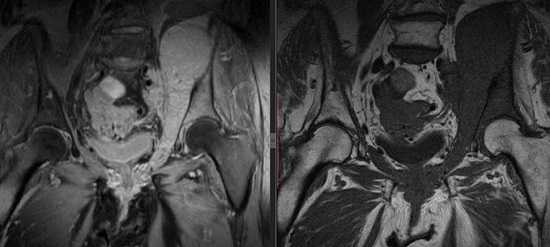

МР-томограмма костей таза

Контрастную МРТ делают поэтапно. После серии нативных снимков прерывают сканирование и вводят больному раствор гадолиния. Инъекцию осуществляют с помощью установленного в вену катетера и автоматического устройства. После заполнения контрастом сосудистого русла в зоне интереса процедуру продолжают.